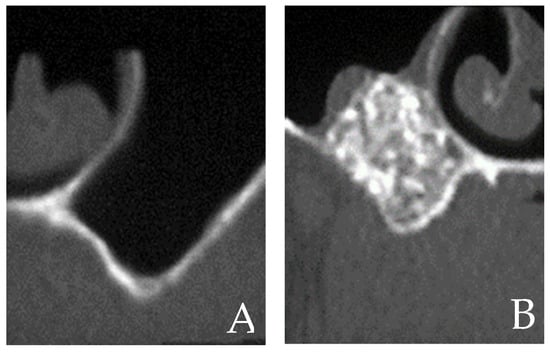

4.3. Surgical Techniques for Sinus Augmentation Using Platelet Derivatives